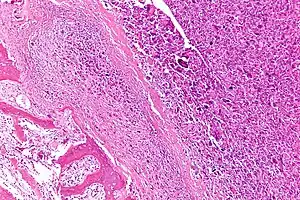

![]() | |

| Intermediate-magnification micrograph of an osteosarcoma (center and right of image) adjacent to non-malignant bone (left-bottom of image): The top-right of the image has poorly differentiated tumor. Osteoid with a high density of malignant cells is seen between the non-malignant bone and poorly differentiated tumor (H&E stain). | |

Microscopically: The characteristic feature of osteosarcoma is presence of osteoid (bone formation) within the tumor. Tumor cells are very pleomorphic (anaplastic), some are giant, numerous atypical mitoses. These cells produce osteoid describing irregular trabeculae (amorphous, eosinophilic/pink) with or without central calcification (hematoxylinophilic/blue, granular)—tumor bone. Tumor cells are included in the osteoid matrix. Depending on the features of the tumor cells present (whether they resemble bone cells, cartilage cells, or fibroblast cells), the tumor can be subclassified. Osteosarcomas may exhibit multinucleated osteoclast-like giant cells.[21]